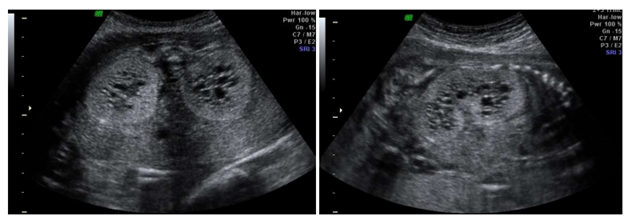

Gestante, 28 anos, primigesta, com 23 semanas de idade gestacional, vem para realização de rotina de ultrassonografia morfológica fetal, apresentando o seguinte achado associado a anidramnia.

Enunciado 4671121-1

Sobre tal patologia em questão, é CORRETO afirmar: